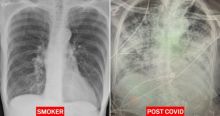

Hasil X-ray Mengungkapkan Jika Paru-paru Pasien Covid-19 Terlihat Jauh Lebih Buruk Daripada Paru-paru Perokok Berat Kesehatan - 15 Jan 2021, 16:09